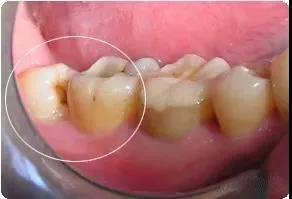

1.蛀牙:如果智齿蛀牙,除了很简单的咬合面不深的蛀牙可以补之外,那些邻接面蛀牙,需要很好的技术,以及蛀得很深,甚至需要根管治疗的,我们一律建议拔除,杜绝后患。

4.清洁不易:由于空间不足的关系,智齿常长得歪七扭八,因此常造成清洁牙齿的困难,以致发生蛀牙现象。